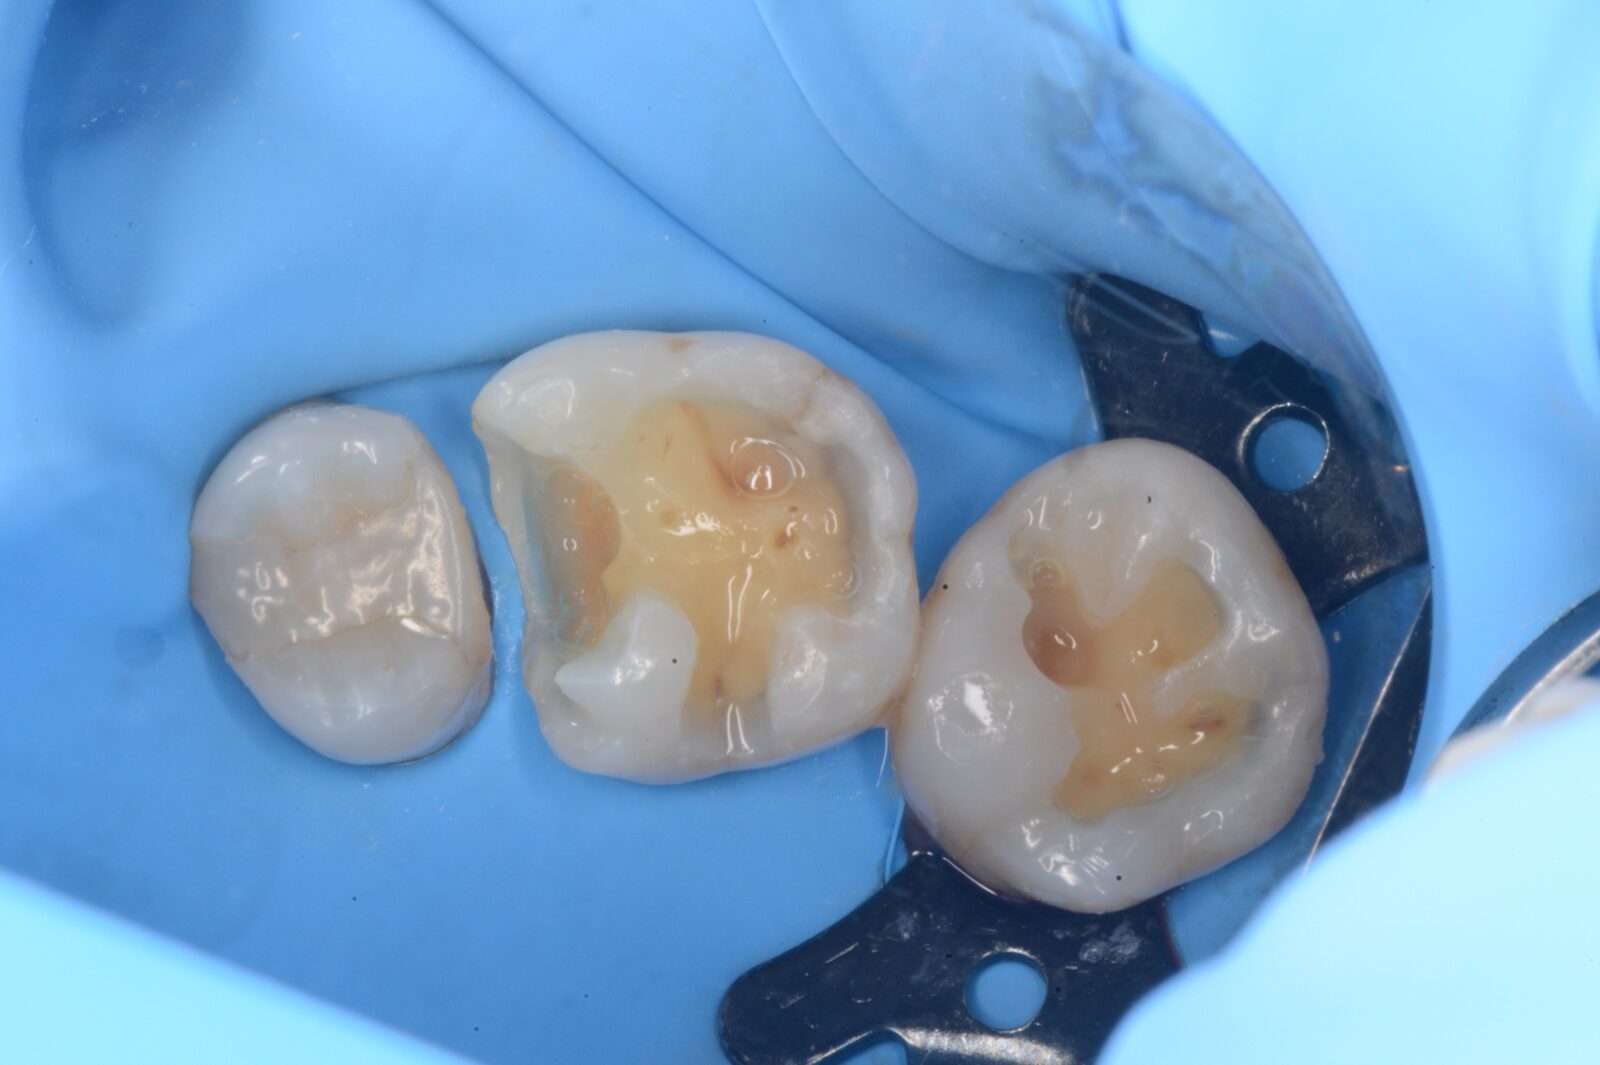

左上6,7ダイレクトボンディング

左上6➡他院で治療したセラミックスの接着不良からの二次感染。 左上7➡コンポジットレジンの接着不良からの二次感染。   ともに、旧充填物と感染歯質を除去後、歯面処理と接着操作を行う。 その後、ダイレクトボンディングにて、充填処置を行い、ティント(ブラウンとホワイト)…